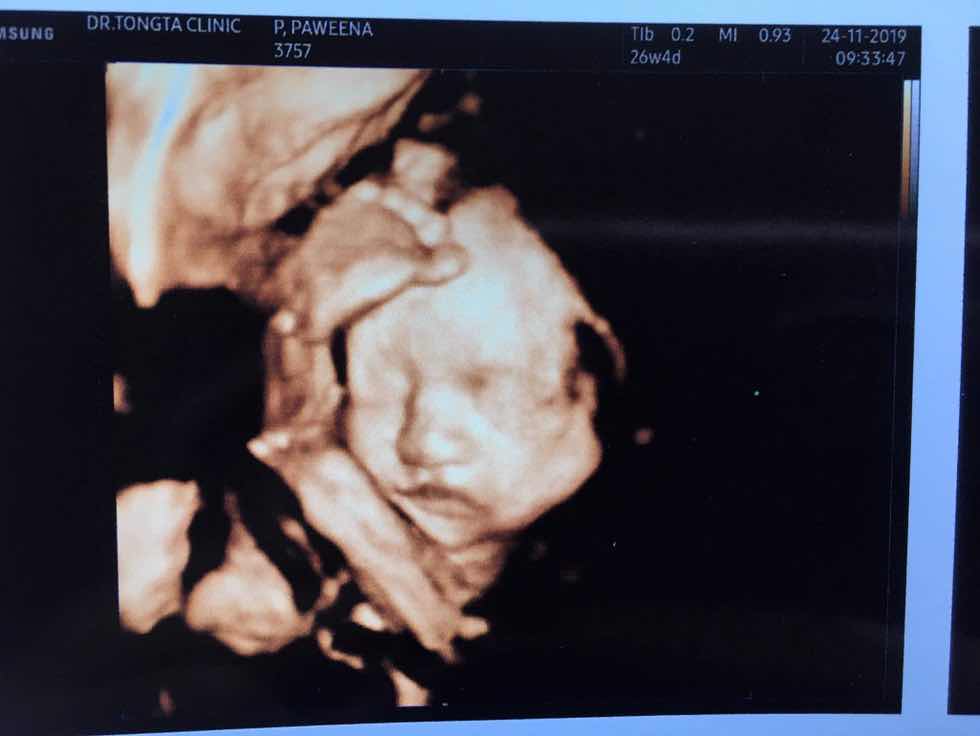

ตอน นั้นประมาณ6เดือน..ตอนนี้36wแล้ว

เห็นหน้าชัดกันมั๊ยคะ บ้านนี้ เอามือบังตลอดเลยค่า หมอเขย่าท้องก็แล้วไม่เอาออกเลยย ??